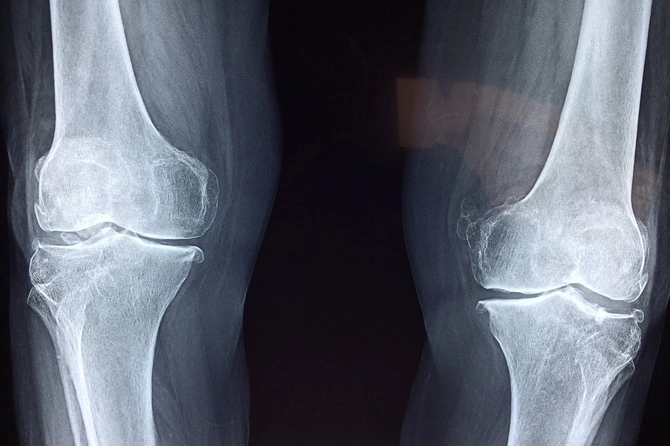

Кроме того, при возрастном снижении плотности костей необходимо принимать препараты с содержанием кальция и других веществ. Женщинам после 50 лет, чтобы снизить риски остеопороза, нужно сдавать анализы на плотность костей. Употребление коллагена также положительно скажется на состоянии связок.